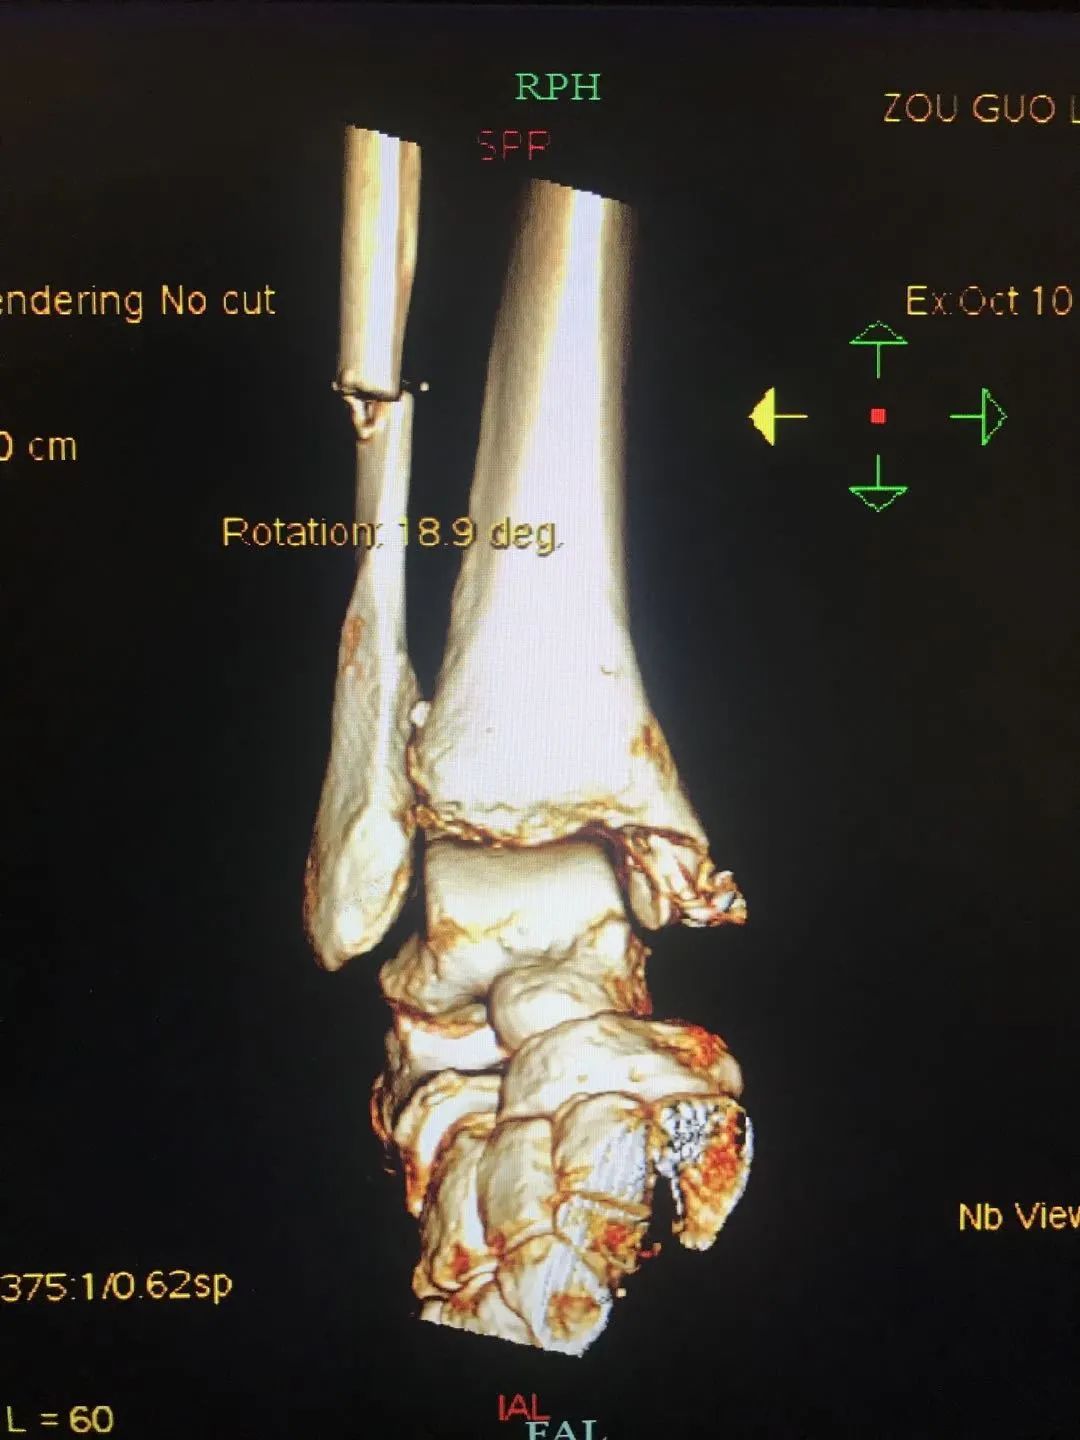

首先就是要将其右腿近十处骨折进行紧急救治。右股骨中段粉碎性骨折、右股骨颈骨折、右胫骨平台骨折、右腓骨小头骨折、右腓骨下段骨折、右髌骨骨折、开放性右踝关节骨折、右第一趾不全离断、右4、5趾缺损、右踝软组织挫裂伤……

喻佳杰医师当即组织紧急多学科会诊。针对邹先生的病情,肝胆外科“下沉”专家张匀教授根据腹部增强CT、病史及相关查体及腹壁漏出的黄色样液体并综合各科室专家意见后判断,提出一个大胆设想。

患者目前的感染病况,很有可能是因为外伤性继发性胰腺炎导致胰液外渗后感染并腐蚀结肠创口,引起了肠漏,坏死组织的吸收、不断漏出的粪便全部都是感染源,若真的有肠道破裂,便是雪上加霜,若不及时处理,很快会发展成感染性休克、多脏器功能衰竭,最终面临死亡,必须手术补漏。